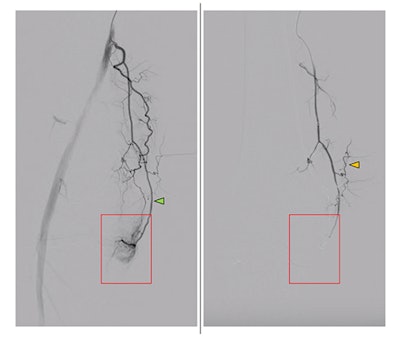

Peri-interventional digital subtraction angiography (DSA) of the descending genicular artery (DSA), a diagnostic procedure to view the inner surface of blood vessels, (green arrow) in a patient with symptomatic knee osteoarthritis of the right leg. On the left, the pre-interventional image with a clearly visible hyperemic blush (red box). On the right, the post-interventional DSA after embolization with Imepenem-Cilastatin. A completely eliminated blush is observed while preserving skin collaterals (orange arrows). Image courtesy of the RSNA.